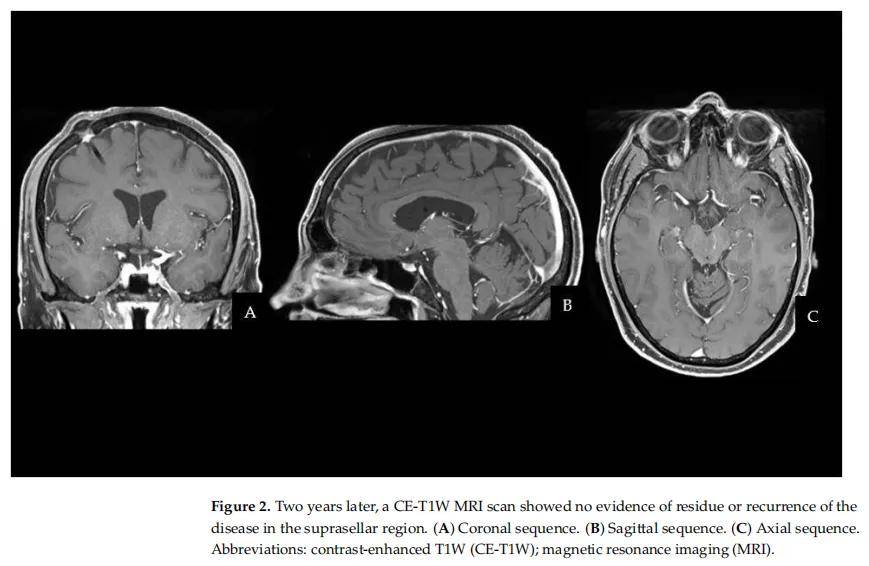

患者术后完全恢复,无神经系统并发症。尽管组织病理学特征与既往的睾丸非生殖细胞瘤性生殖细胞肿瘤不同,但形态学和免疫表型检查证实该病变为混合性生殖细胞肿瘤(Oct4+、SALL4+、CD117+;Ki67约 10%)。术后 1 个月,患者开始接受 2 个周期的顺铂、依托泊苷和异环磷酰胺(PEI)化疗,随后接受 18 次常规放疗(CRT)。治疗结束后 3 个月和 6 个月的MRI扫描未记录到疾病复发。2 年随访脑部MRI如图2所示,未显示手术区域有任何再生迹象。除永久性尿崩症外,患者无其他内分泌疾病或神经系统后遗症。尽管有医疗建议,患者及其家属未接受任何用于排查癌症易感综合征的基因检测。

▲图2 两年后,CE-T1W MRI扫描显示鞍上区无疾病残留或复发迹象